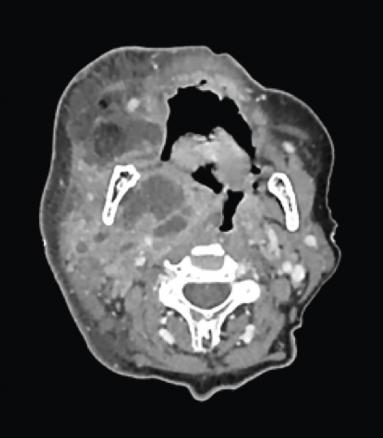

Scanner cervico-facial avec injection : infiltration sous-cutanée cervico-faciale droite diffuse, associée à un abcès de 6 x 6 cm allant de l’espace parapharyngé droit à la fosse infratemporale, occupant la région parotidienne. Thrombophlébite jugulaire interne et externe homolatérale (figure ).

Scanner cervico-facial avec injection : infiltration sous-cutanée cervico-faciale droite diffuse, associée à un abcès de 6 x 6 cm allant de l’espace parapharyngé droit à la fosse infratemporale, occupant la région parotidienne. Thrombophlébite jugulaire interne et externe homolatérale (